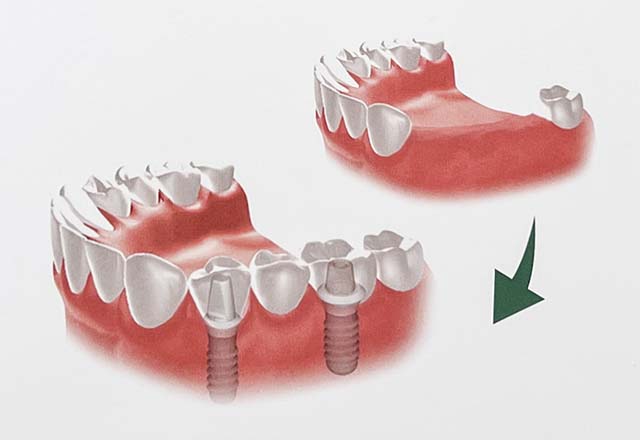

| 治療の説明 | 他院で抜歯を行った後、入れ歯を勧められましたが、入れ歯には抵抗があり、他の治療方法を探されていました。 その結果、当院でインプラント治療を希望されました。 患者様のご希望により、歯の欠損部分をインプラントで補い、上部構造(被せ物)にはフルジルコニアセラミックのブリッジを選択されました。 そのため、見た目や噛み心地がより天然歯に近い仕上がりとなりました。 |